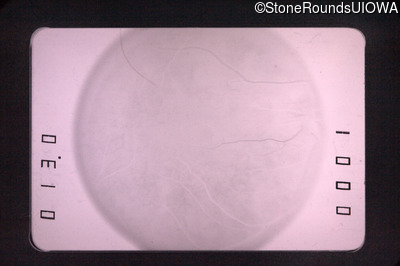

Fundus Photography - Left - 20/30 +1

Exemplar